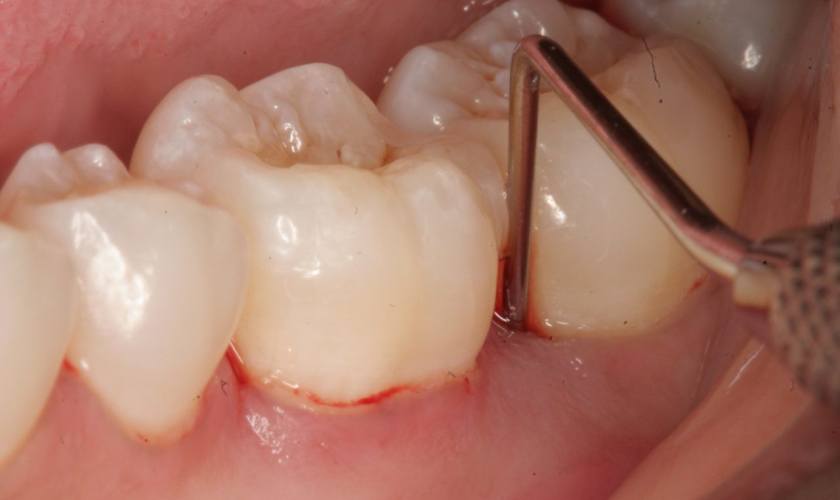

- Cạo vôi răng: Bác sĩ sử dụng máy cạo vôi răng siêu âm để loại bỏ mảng bám, vôi răng ra khỏi bề mặt răng và bên dưới nướu, từ đó giúp nướu phục hồi và giảm viêm.

Cạo vôi răng để khôi phục sức khỏe của nướu